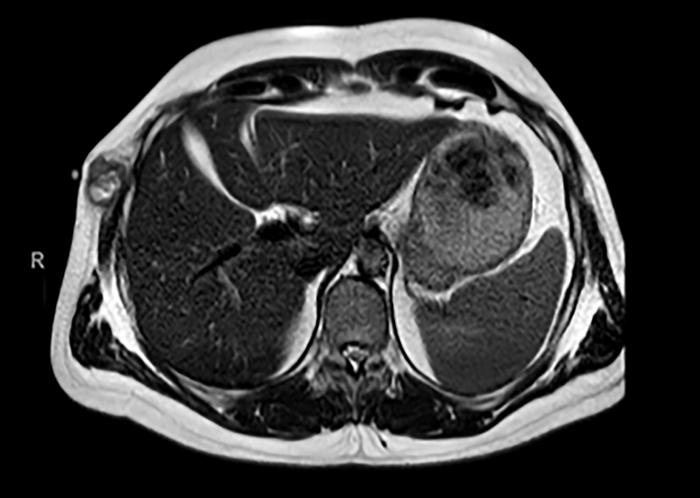

In their paper, researchers Marta Arregui, Antonio Calles, María del Mar Galera, Ana Gutiérrez, Carlos López-Jiménez, Carolina Agra, Adriana Fernández, Natalia Gutiérrez, María de Toro and Rosa Álvarez from Gregorio Marañón University Hospital and Fundación Jiménez Díaz University Hospital in Madrid, Spain, document a remarkable clinical and metabolic response in a case of metastatic BRAF V600E-mutated glomangiosarcoma treated with the combination of encorafenib and binimetinib.

They report on a 45-year-old male patient with stage IV malignant GT carrying a BRAF V600E mutation, who was treated systemically with encorafenib and binimetinib. This approach led to a swift clinical and radiological improvement.

“To our knowledge, our patient represents the first reported case of a metastatic malignant GT successfully treated with BRAF and MEK inhibitors, achieving a long-lasting complete morpho-metabolic response.”